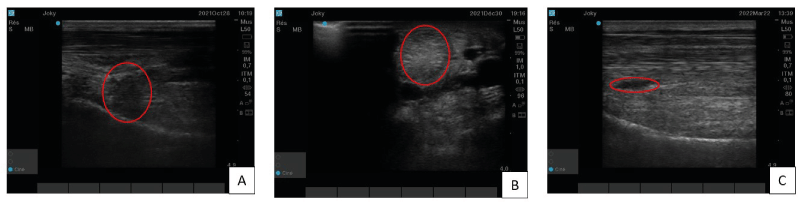

A 7 years-old gelding used for jumping was shown for a lameness graded 3/5 on the right hindlimb using the scoring scale from the American Association of Equine Practitioners. A desmitis of the proximal branch of the suspensory ligament was diagnosed. This horse was first treated with platelet-rich plasma (PRP) but only a partial improvement was observed 3 months after PRP injection (Figure 2A).  In view of these unsatisfactory results, it was decided to treat him with two-point injections of TDSCs under ultrasound control. One month post-treatment, ultrasound imaging did not show significant improvement. A second TDSCs injection was then performed with the same approach. Six weeks later the ultrasound image showed clear improvement with disappearance of the hypoechogenic zone but a small hyperechogenic zone remained (Figure 2B). This zone progressively disappeared within 3 months post-injection (Figure 2C). During this time the horse came gradually back to work and the clinical evolution remains satisfactory four months after the second injection.

Figure 2. Case one’s proximal branch of the suspensory ligament ultrasound imaging : A) Longitudinal section, three months after PRP treatment,. In red circle, a hypoechogenic zone which is the sign of the ligament’s lesion.  B) Transversal section, six weeks after second tendon-derived mesenchymal stem cells injection. In this image, the red circle is on the hyperechogenic zone. C) Longitudinal section, four months after tendon-derived mesenchymal stem cells second injection. This one, show a homogenous and linear organisation but in the red circle, a little hypoechogenic zone persists